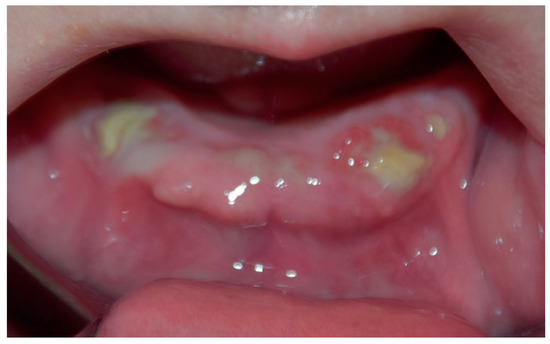

2.2. Clinical Findings